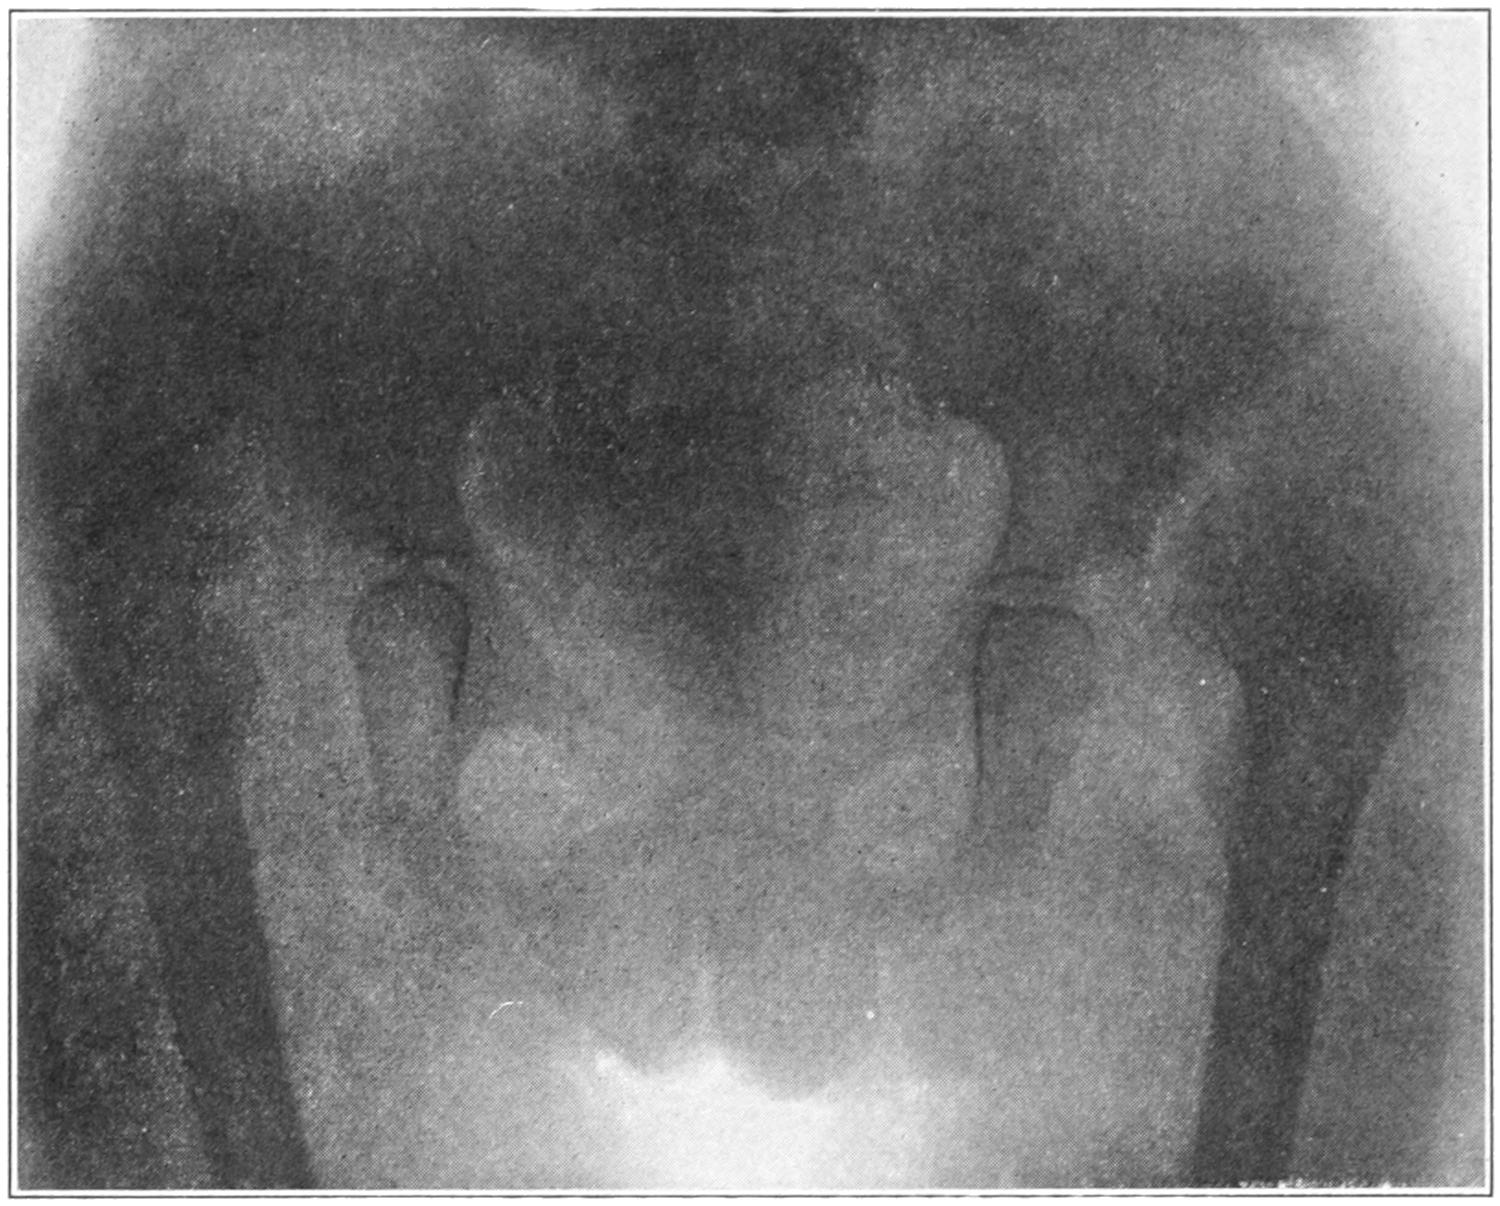

Fig. 1

Congenital hypertrophy: gigantism of both lower extremities. (Case of Dr. Graefe [Sandusky].)